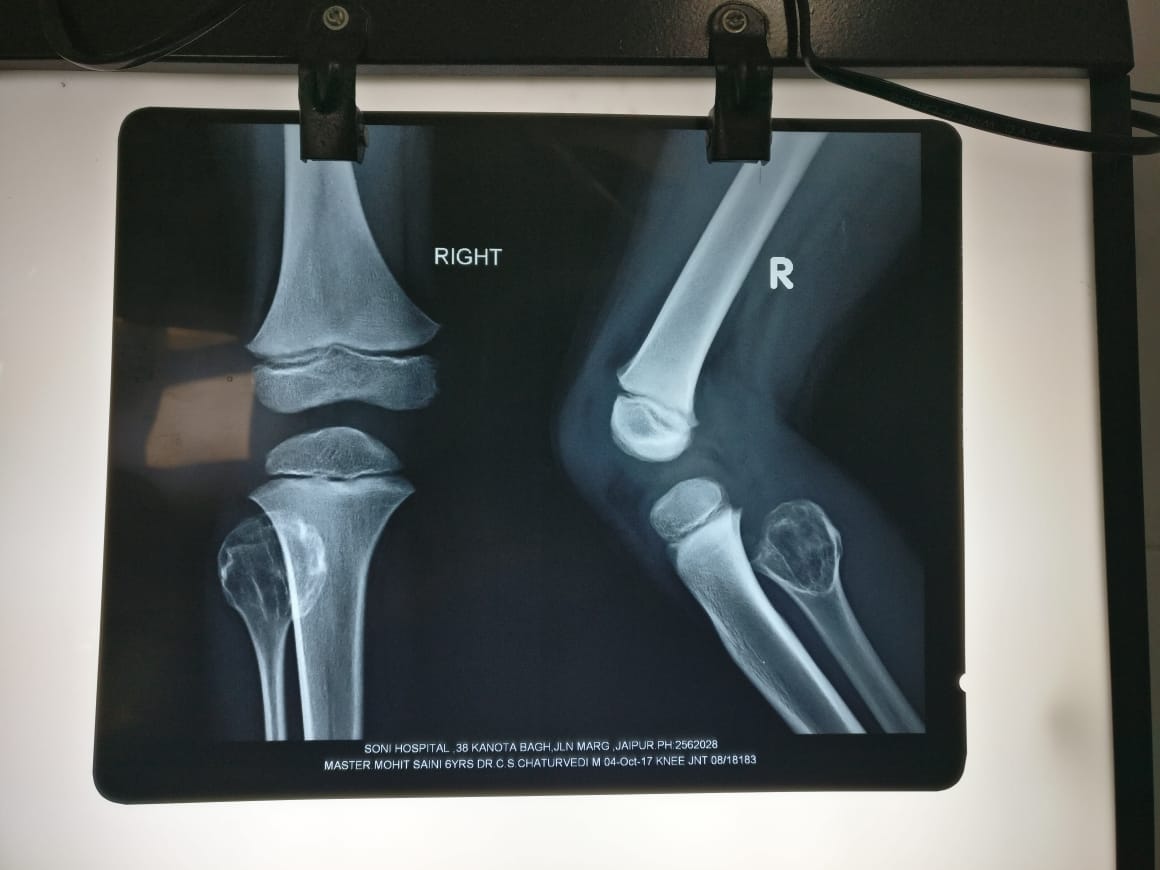

Elbow fractur

Elbow fracture